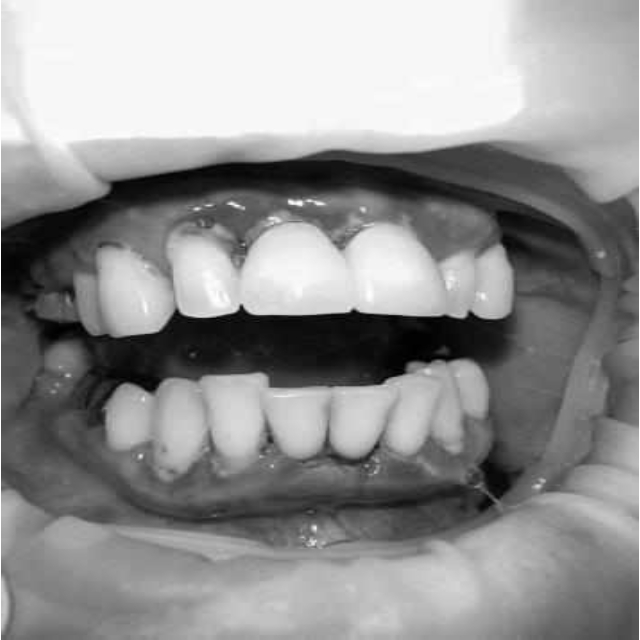

За пародонтологическим лечением обратилась женщина 61 года с жалобами на неприятный запах из полости рта, кровоточивость десен при чистке зубов, подвижность зубов, несостоятельность ортопедических конструкций.

Ранее у пародонтолога не наблюдалась. При осмотре выявлены: неудовлетворительная индивидуальная гигиена полости рта, пародонтальные карманы до 7 мм, обильная кровоточивость и гноетечение из пародонтальных карманов, подвижность зубов 4.2, 4.1, 3.1, 3.2 II степени, обильные над- и поддесневые зубные отложения (рис. 1). На ортопантомограме отмечается резорбция костной ткани до ½ длины корня, очаги остеопороза (рис. 2). Пациенту был поставлен диагноз хронический генерализованный пародонтит тяжелой степени тяжести. При осмотре была составлена пародонтограмма с использованием компьютерного зондирования (рис. 3).

Рис. 2. Ортопантомограмма исходной ситуации пациента состояния полости рта

Через 6 месяцев при осмотре выявлен удовлетворительный уровень индивидуальной гигиены, отсутствие участков кровоточивости и гноетечения (рис. 4), пародонтальные карманы уменьшились в размерах (рис. 5). Пациент отмечает значительные улучшения. После стабилизации пародонтологического статуса пациент направлен для дальнейшего ортопедического лечения.

Рис. 4. Динамика результата через 6 месяцев